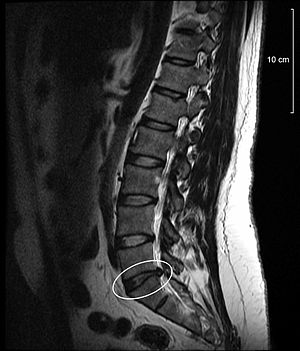

<Ç㸮µð½ºÅ© ȯÀÚ MRI>

Ç㸮µð½ºÅ©¶õ 33°³ ôÃß Áß °æÃß 1~7¹ø, ¿äÃß 1~6¹ø ,ÈäÃß 1~12¹ø ÀÌ Ãß°£ÆÇÀÌ Á¦ÀÚ¸®¸¦ ¹þ¾î³ª

ÁÖº¯ ½Å°æÀ» ¾Ð¹ÚÇÏ¿© ÅëÁõ ¹× ±âŸ ÀÌ»óÀÌ ¹ß»ýÇÏ´Â °ÍÀ» ¸»ÇÕ´Ï´Ù.